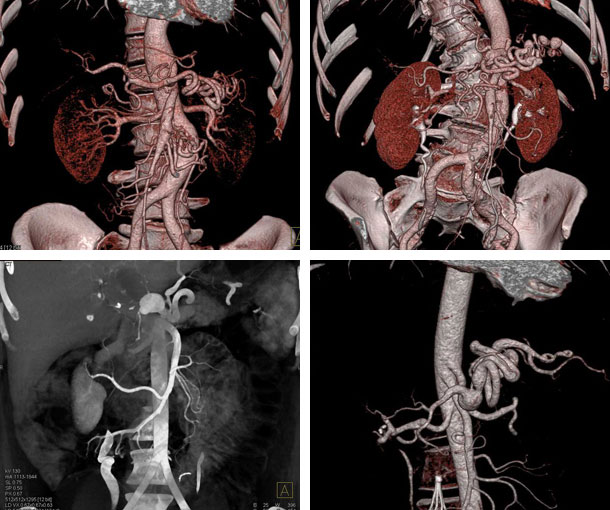

Ehlers-Danlos Syndrome (EDS) CT Findings

- May involve multiple vascular segments

- Aneurysms (single or multiple)

- Dissections (single or multiple)

- Occlusions (single or multiple)